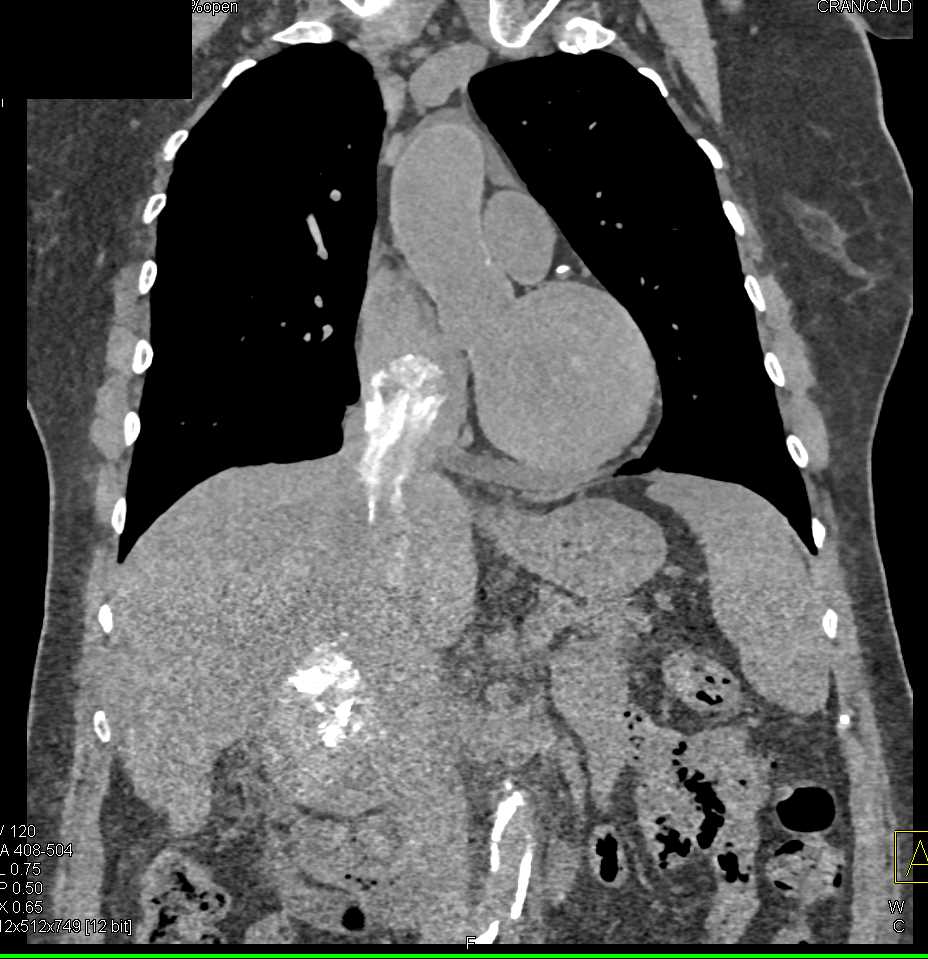

Pericardial Cyst